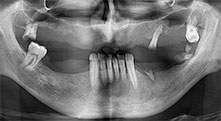

Bratu: Utilizamos los insertos de forma rutinaria para la extracción de injertos óseos y la ranuración de las crestas alveolares. También utilizamos las Piezomed B6/B7 para practicar osteotomías en dientes retenidos y no retiramos implantes que pueden conservarse. Todas estas son indicaciones que requieren cortes profundos y limpios.

Bratu: Preferimos realizar las osteotomías en la línea oblicua externa de la cara posterior del maxilar inferior, y no en la región situada entre los orificios. Tras realizar una incisión en los tejidos blandos, utilizamos las nuevas sierras para definir el contorno de la osteotomía. De este modo, conseguimos una preparación completa en prácticamente el 80 por ciento de los casos. Por otro lado, en algunas ocasiones también utilizamos otros insertos piezoquirúrgicos, así como un cincel para mover el injerto. Para nosotros, esta es una técnica de intervención muy eficaz.

Bratu: Nos gusta utilizar la técnica de sándwich para realizar aumentos en la cara lateral del maxilar inferior. En este procedimiento, se utiliza la sierra piezoquirúrgica para preparar una tapa ósea, mientras que el fragmento crestal se fija con microtornillos. Entre medias, colocamos una combinación de hueso autólogo y material óseo adicional xenógeno. Y con ello obtenemos un rendimiento muy fiable. Asimismo, en los ranurados de la cresta alveolar del maxilar inferior, nunca se puede prescindir de cortes verticales suficientemente dimensionados, pues, de lo contrario, los huesos pueden fracturarse fácilmente.